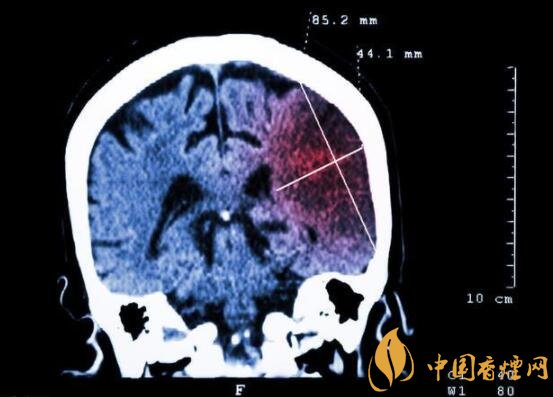

一般而言,急性腦梗塞與長期吸煙有非常密切的聯(lián)系。有長期煙齡遇到肢體活動不順,做頭顱核磁共振檢查往往查出一側大腦中動脈閉塞的可能性很高。由此可見,吸煙確實與中風存在一定聯(lián)系。